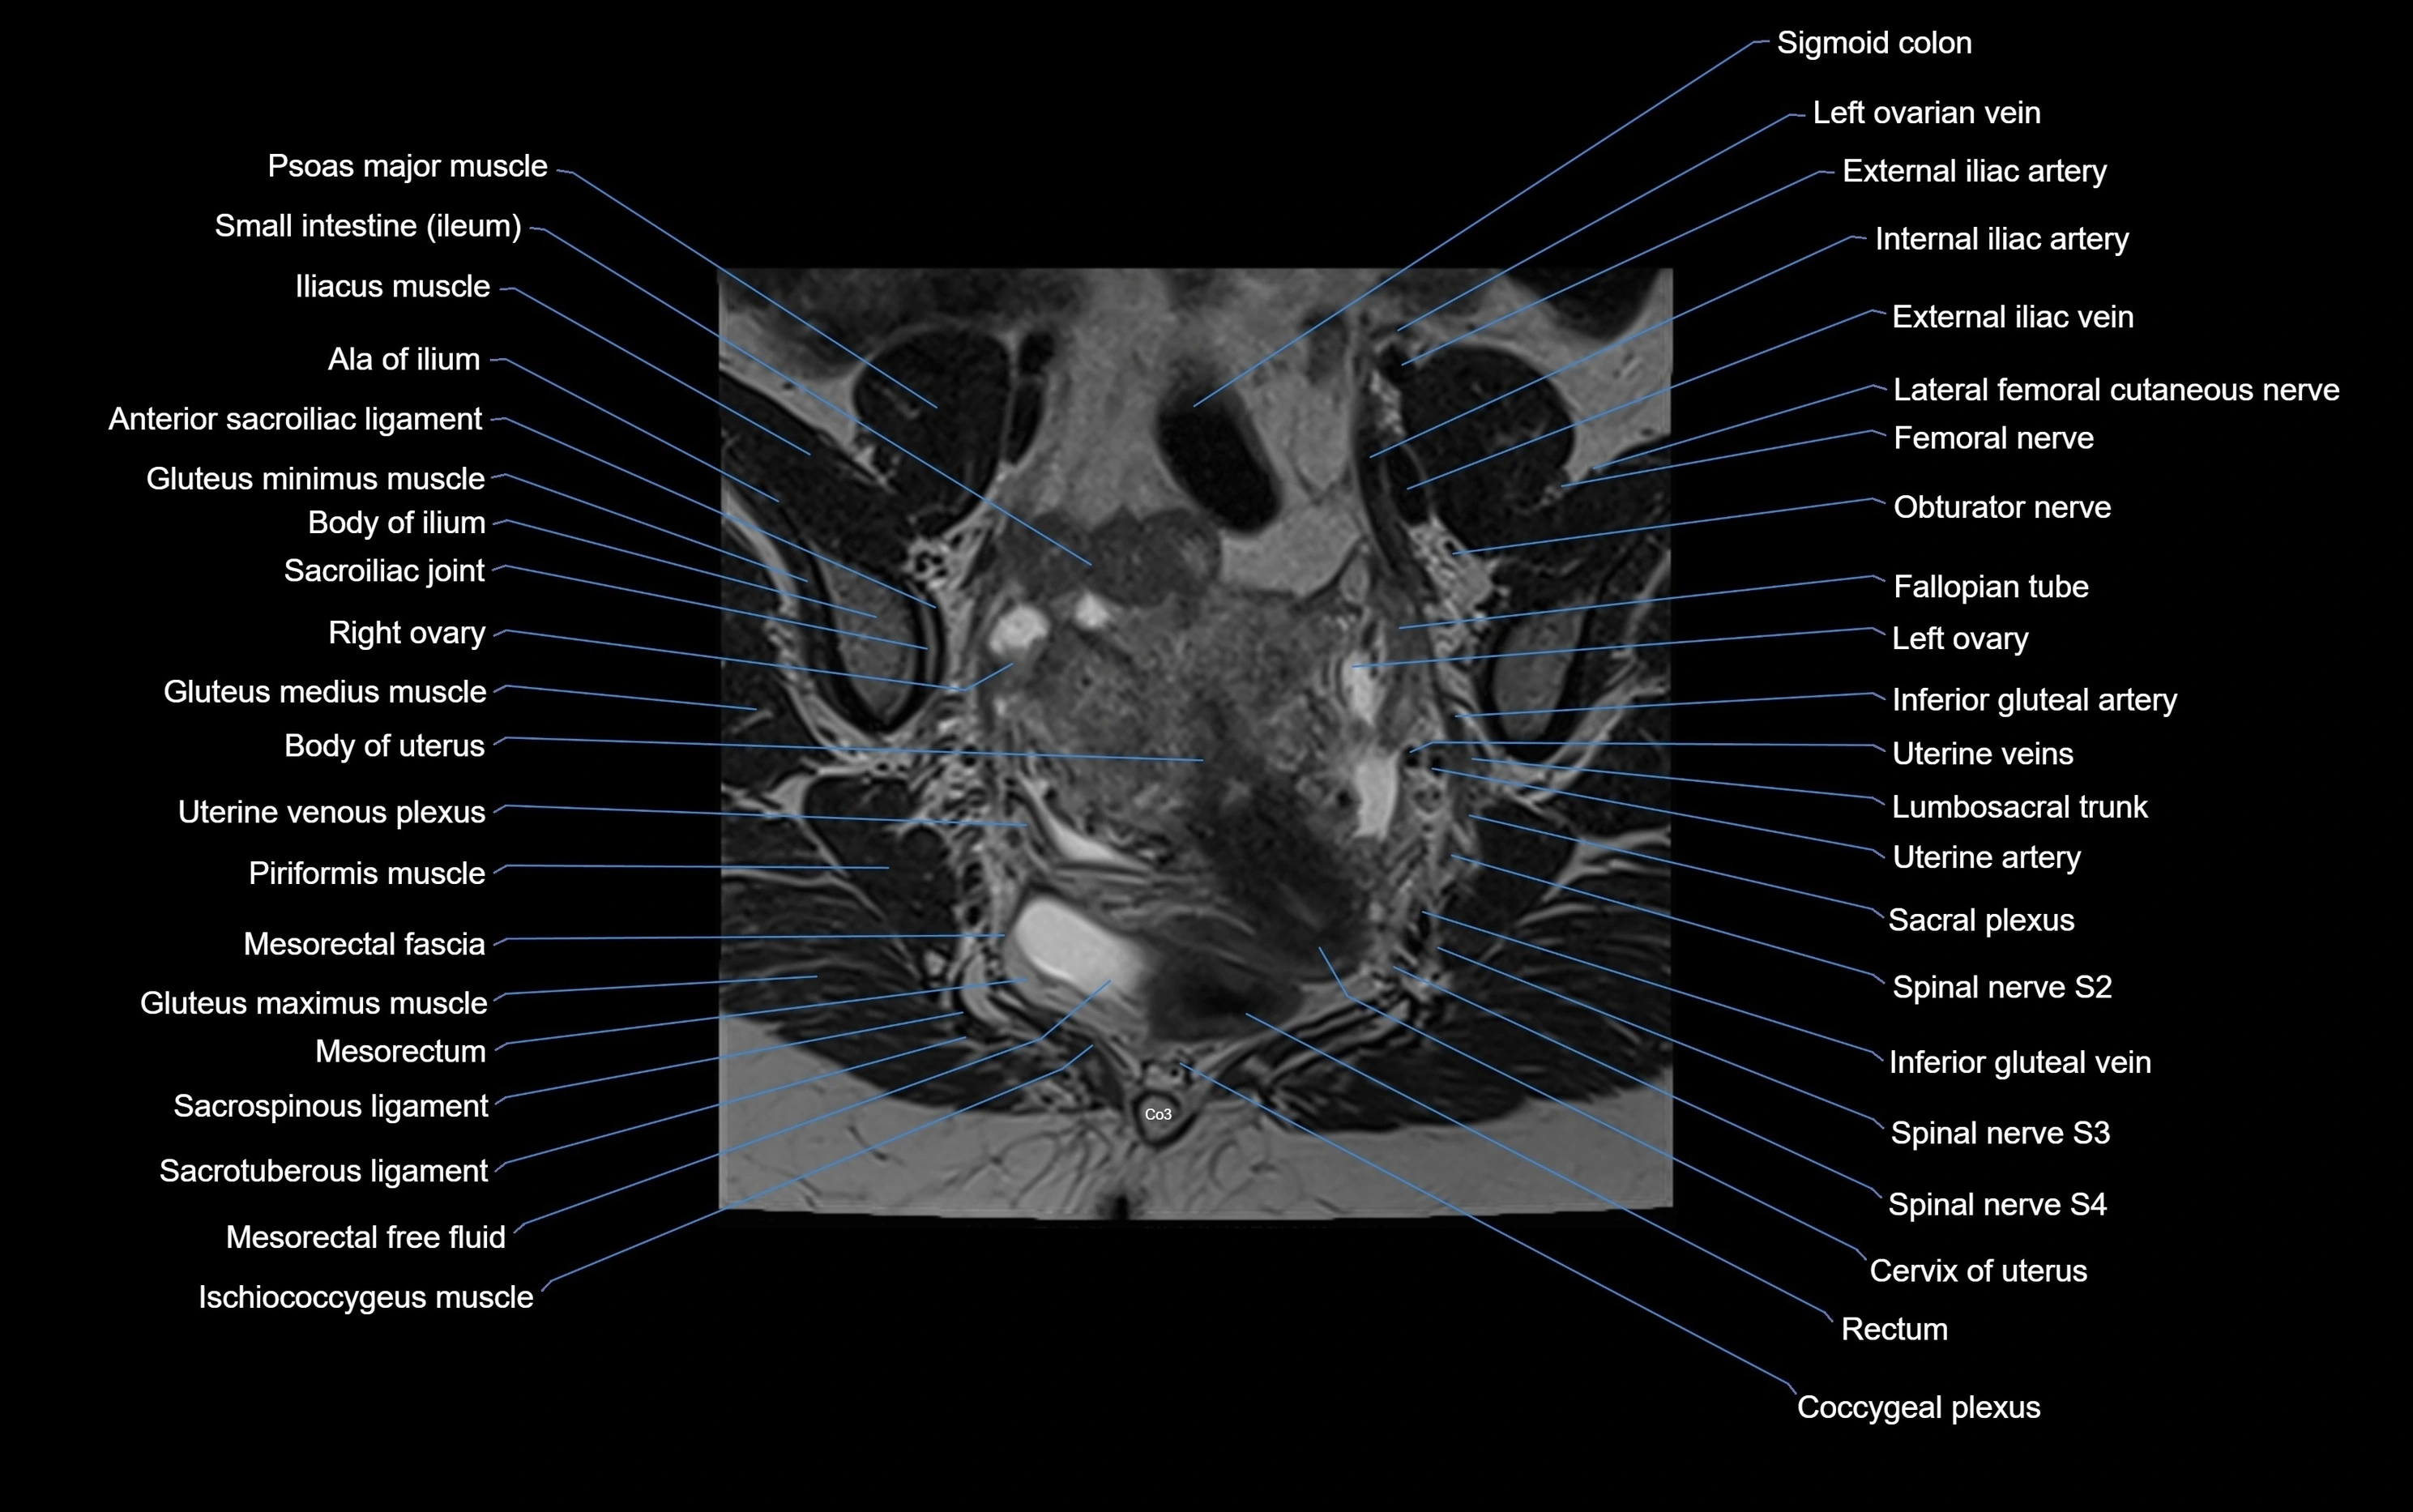

MRI image

image